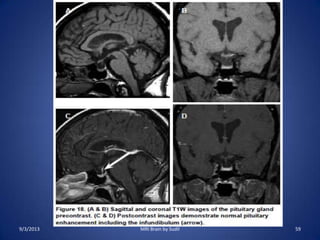

Pituitary fossa

• Indications:

– To detect sellar and parasellar lesions, to delineate intrusion into

surrounding structures.

– Hormonal disturbances(amenorhea, hyperprolactinemia,

acromegaly),

– Suspected or known microadenoma or macroadenoma,

– Pituitary apoplexy and sudden visual loss.

• Sequences :

– Routine protocol

– Coronal T1SE through the sella

– Post contrast T1SE with fat sat. in Sagittal and coronal plane

through the sella

– Post contrast T1SE with fat sat in the axial plane through the

whole brain.

9/3/2013 57MRI Brain by Sudil

Brain MRI protocol (Pituitary)

• Coronal sequence

• Plot on mediosagittal

localizer superior to

sella.

• Slice thickness: 2mm

• Slice Interval : 0-20% of

thickness

• 2 sat. slab

• Small FOV

9/3/2013 58MRI Brain by Sudil

9/3/2013 59MRI Brain by Sudil